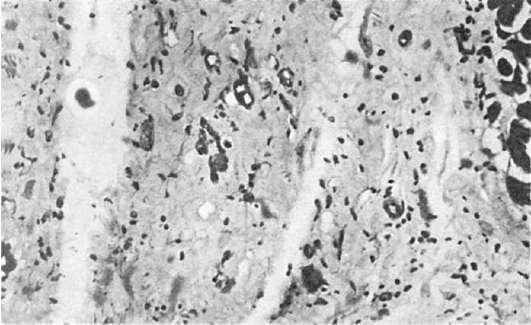

Патологическая анатомия. Наиболее часто изменения развиваются в скелетной мускулатуре, в мышцах глотки, гортани, диафрагмы, глазных мышцах. Мышцы становятся бледно-желтыми, отечными. В подкожной клетчатке, мышцах появляются очаги кальциноза. При микроскопическом исследовании постоянно обнаруживаются

дистрофические изменения мышечных волокон, в них исчезает поперечная исчерченность, уменьшается содержание гликогена, резко понижается активность ряда ферментов. Многие мышечные волокна некротизированы, и в очагах некроза видно выпадение извести в виде мелких зерен. В соединительнотканной строме мышц, которая вовлекается в процесс вторично, развиваются отек и воспалительная реакция. В инфильтрате преобладают лимфоциты, макрофаги и плазматические клетки (рис. 182). Скопления лимфоцитов и макрофагов особенно выражены по ходу микрососудов, со стороны эндотелия капилляров отмечаются пролиферация и десквамация, вплоть до полного закрытия просвета.

Рис.

182. Дерматомиозит. Дистрофические изменения мышечных волокон, клеточная инфильтрация межуточной ткани